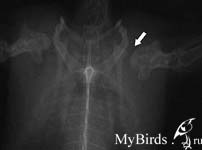

Перелом лучевой кости, смещенный

Перелом лучевой кости после внутрикостной фиксации 0,4 мм канюлей |